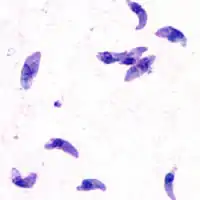

Tachyzoiter

I tachyzoite-stadiet formerer organismen sig hastigt i en hvilken som helst celle i en mellemvært, samt overflade væv der ikke sidder i tarmen hos den ægte vært. Tachyzoiten er halvmåneformet, og 2-6 µm lang. Selvom tachyzoiter kan glide, bøje og rotere, har den ingen synlige midler til at sætte sig i bevægelse, som f.eks. cilia eller flageller.

Tachyzoiten adskiller sig rent strukturelt kun fra bradyzoiten ved det at cellekernen sidder centralt i cellen, mens den i bradyzoiten sidder forskudt mod bagenden. Med hensyn til livscykus, er bradyzoitens dvaleperiode før den udvikles til ooyster efter indtagelse af katten kortere (3-10 dage) end hvis katten indtager tachyzoiter (≥14 dage).